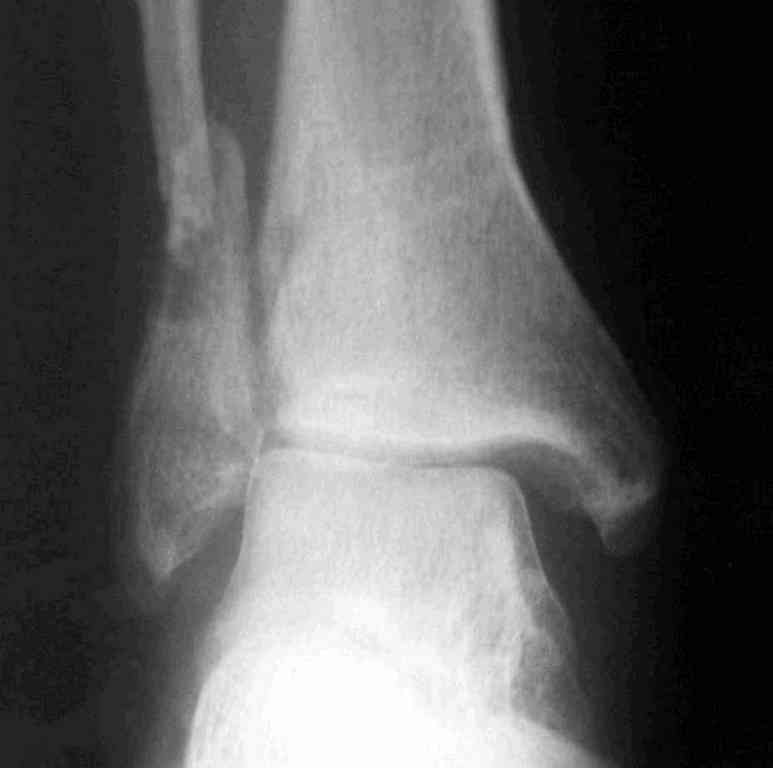

Вторая пациентка 34 лет, перелом получала в Испании, где от операции отказалась, дома по приезду сняла скотчкаст и лечилась у костоправов, нагрузка с 3 недели. Операция через 3 мес после травмы. Остеотомия м-б кости, фиксация пластиной, восстановление МБС. Так как медиальная лодыжка подтянулась, суставная щель на ЭОП контроле нормализовалась ограничились латеральным доступом. Реконструкцию заднего края не пытались сделать тк там уже прослеживалась консолидация, а сминать эпиметафиз не хотелось. В настоящее время ходит с тростью \три месяца после операции\, сустав нестабилен-слабость дельтовидной связки. Супинатор и плотные кроссовки дают возможность длительно ходить. Первый снимок сделан в Испании после репозиции, второй через 2 месяца после травмы перед операцией, третий-через 3 мес после операции.

Спасибо за вложенную схему , ранее она нам не попадалась.Согласен с Алексеем, что в обоих случаях не удалось восстановить длину фибулы.По вопросу о МБС, в первом случае после 8 месяцев синдесмоз был выполнен плотной рубцовой тканью, которую необходимо было убрать для репозиции фибулы в вырезку и винт действительно был введен с компрессией, во втором случае МБС не открывался и компресии не задавлось.Может дистрофия эпифиза все же следствие 5 месячной нагрузки с нестабильным суставом и компрессии тараном, тк вес пациента достаточно высок. По второму наблюдению необходимо определиться с тактикой, при пронации стопы отчетливо определяется слабость дельтовидной связки-перерастянута ходьбой в нестабильном суставе? Показана ли надлодыжечная варизующая остеотомия?